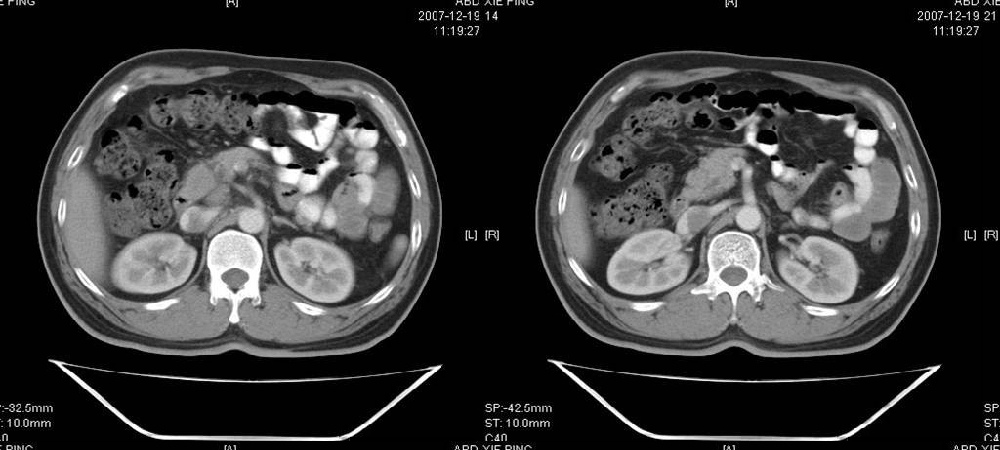

临床病史:患者,男,53岁,因反复上腹部饱胀不适2+月,在餐后或饥饿时明显,伴呃逆,无呕吐、呕血,无腹痛腹泻;2年前腹腔镜胆囊切除,否认肝炎、结核等病史。

体格检查:一般情况可,腹平软,全腹无压痛,无反跳痛,未扪及包块,肝脾未及,肠鸣音正常。白细胞6.03×10e9/l,中性粒细胞3.32×10e9/l,淋巴细胞2.06×10e9/l

胰腺头部低密度囊性病灶,边缘清楚,增强后囊壁略强化。考虑:胰头假性囊肿!

胰腺头部(或肝脏尾叶部)低密度囊性病灶,边缘清楚,增强后囊壁略强化。考虑:胰头假性囊肿. 或肝脏尾叶部囊肿。

考虑十二指肠憩室。从影像上看,病变位于下腔静脉前胰头后方十二指肠内侧,肝尾叶受压,说明病变来源于后腹膜;胰胆管成像胰管和胆道未见扩张,总胆管中段受压未显示,上下段正常,所以不考虑来源与于肝尾叶和总胆管的囊肿。考虑为十二指肠憩室或小网膜囊肿。

楼上高手,本例的确是一例十二指肠憩室.